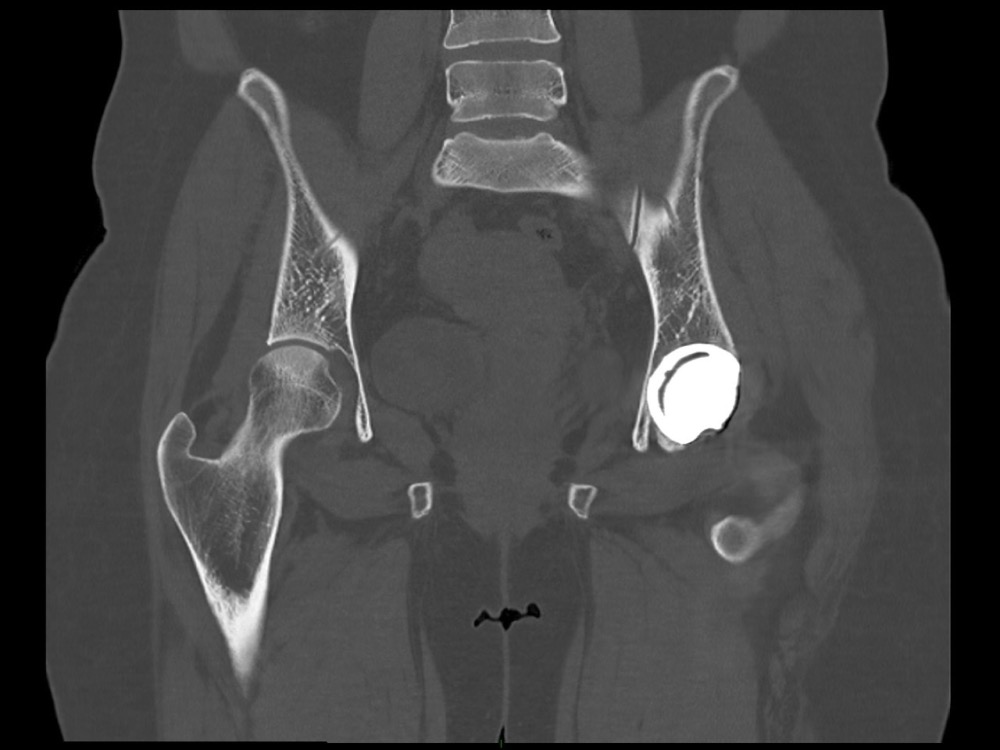

Aboudaram / Burns 11/01/2023